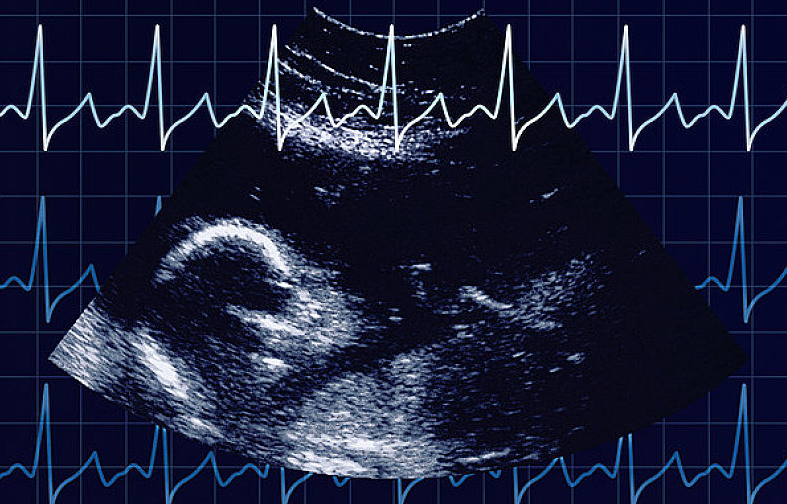

通過胎心監(jiān)護能了解到胎兒在子宮內的情況,因此,孕媽們應按時產檢,從孕32周(患有妊娠高血壓等疾病的孕媽從孕28周)開始就要進行胎心監(jiān)護。

胎心是胎兒的心跳,反映胎兒在宮內狀態(tài)。

當各種原因引起胎兒缺氧時,胎心很敏感地會出現變化。胎兒正常的胎心率為110~160次/分,正常的胎兒心率隨子宮內環(huán)境的不同,時刻發(fā)生著變化,胎心率的變化是中樞神經系統(tǒng)正常調節(jié)機能的表現,也是胎兒在子宮內狀態(tài)良好的表現。若胎心率分或>160次/分,持續(xù)10分鐘以上,稱為胎心過緩或胎心過速。